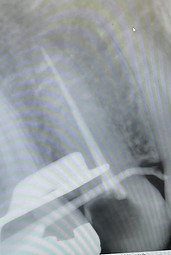

Endodontics

RCT

RCT later restored with crown